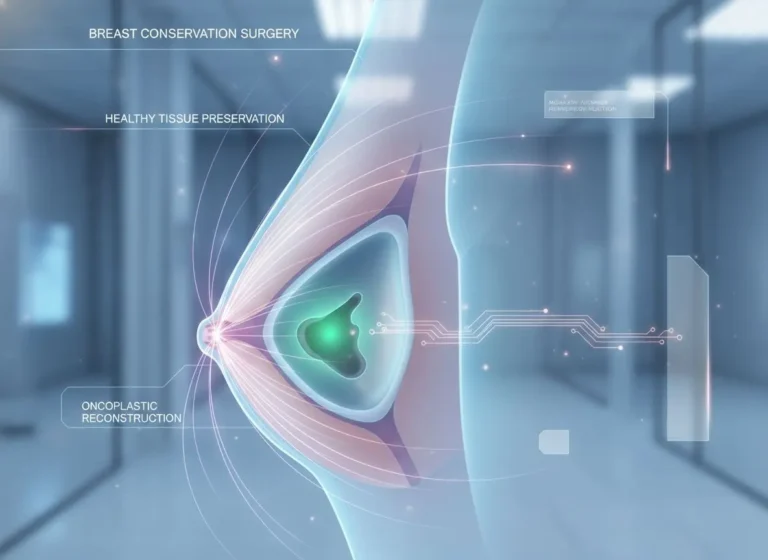

The curtain lifts, revealing the essence of what lies ahead; curiosity meets direction in this unfolding moment Breast Conservation Surgery in Borivali.…

Breast Conservation Surgery In Mira Road If you’re reading this because either you or someone you love has recently been diagnosed with…

Introduction Hearing the words breast cancer can feel overwhelming. If you’re here, you or someone close to you might be facing difficult decisions. One…

Healing Beyond Surviving If you’re reading this, it’s likely that you or someone close to you has been affected by breast cancer.…